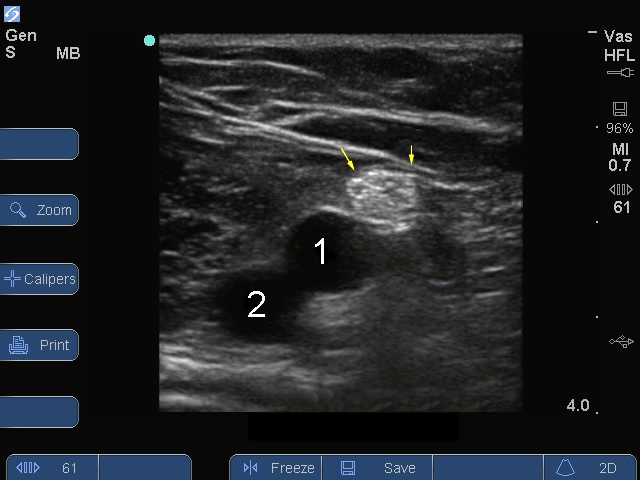

S Series : Image, Nerf sciatique, vaisseaux poplités

Flèches : Nerf sciatique

Veine

Artère